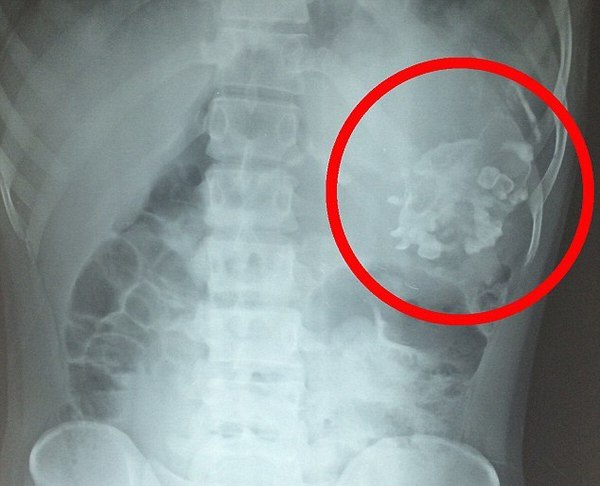

21-летний Нарендра Кумар с детства страдал всевозможными недомоганиями, включая потерю веса. Его семья не понимала, что с ним происходит, пока однажды сканирование в больнице не выявило внутри живота парня в области желудка необычную опухоль

Врачи были удивлены, обнаружив массу из костей, волос и зубов — весом 2.5 кг — внутри живота Наренды.

Паразитирующая масса ‘подпитывалась’ Кумаром, после чего сформировалась целая пуповино-подобная структура, подключенная к кровеносной сети индийца.

В конце концов, Наренде был поставлен диагноз ‘утробный плод в плоде’ или ‘эмбрион в эмбрионе’ (‘foetus in fetu’). На данный момент, во всем мире зарегистрировано всего около 200 подобных случаев.

Состояние возникает, когда на ранних стадиях вынашивания близнецов один из плодов проникает в другого через пуповину.

Доктор Раджив Синг стал первым, кто выполнил надлежащее медицинское обследование, в том числе ультразвуковое, а также компьютерную томографию, прежде чем удалось поставить точный диагноз.

Затем доктора удалили паразитирующий плод хирургическим путем. Извлеченная масса была 20 см в длину, с целой ‘магистралью’ волос длиною два метра.

Синг сказал: ‘За время трехчасовой операции мы удалили ту самую массу, недоразвитого младенца, имеющего волосы, зубы, слабо развитую голову, костную структуру грудной клетки и позвоночника с большим количеством желтоватой амниотической жидкости, такой, как внутри плодных оболочек’.